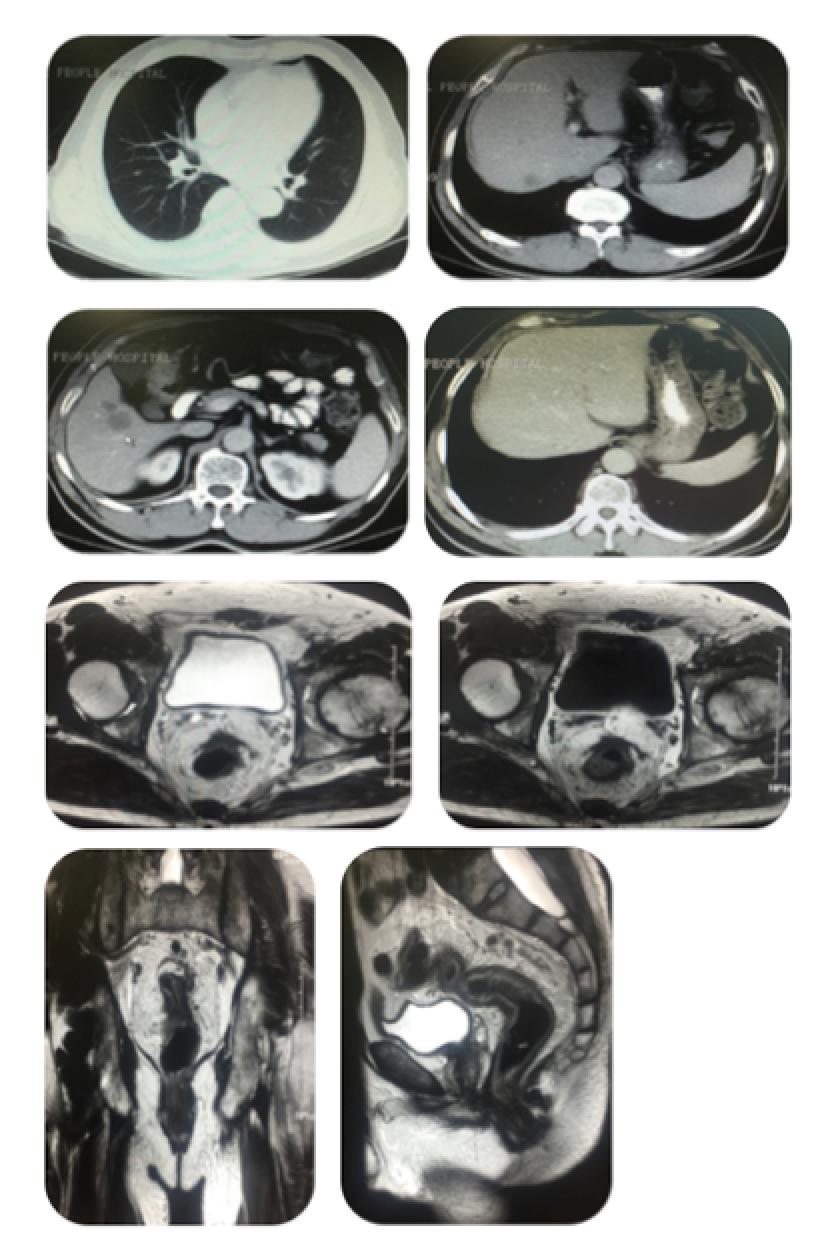

一线治疗疗效评估—影像学检查

2015-9-24

胸部+上腹部CT示:1.右肺斜裂走行区小结节,较前(2015-8)变化不著。2.肝脏多发低密度影,结合病史考虑转移瘤,较前片(2015-8)病灶有所缩小。3.胰腺周围淋巴结轻度肿大。

盆腔MRI:1.直肠上段异常所见,考虑直肠癌,另直肠左侧方及后方多发结节样及条片状异常信号影,大部分融合,局部与直肠病变分界不清,考虑肿大淋巴结,肿瘤分期T3N2a期 2.盆腔及双侧腹股沟区多发肿大淋巴结,部分肿大。

2015-11-4

胸部+上腹部CT示:1.右肺斜裂走行区小结节,较前(2015-9)变化不著。2.肝脏多发低密度影,结合病史考虑转移瘤,较前片(2015-9)病灶有所缩小。3.胰腺周围淋巴结轻度肿大。

盆腔MRI:1.直肠上段异常所见,考虑直肠癌,另直肠左侧方及后方多发结节样及条片状异常信号影,大部分融合,局部与直肠病变分界不清,考虑肿大淋巴结, 2.盆腔及双侧腹股沟区多发肿大淋巴结,部分肿大。以上病变较前片(2015-9-24)直肠上段、直肠左侧及后方病变略有所缩小,余变化不著。